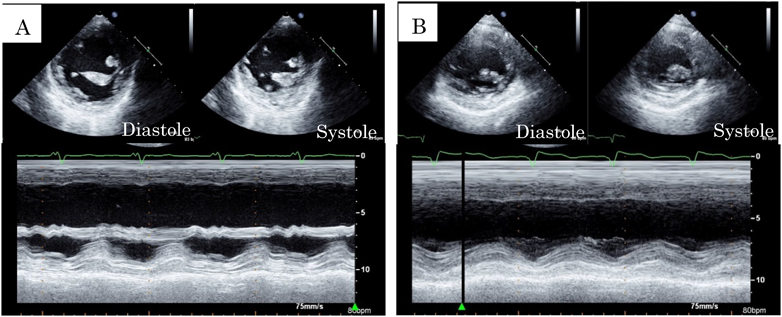

Fig. 4 Transthoracic echocardiography

Pre- (A) and post-cardiac resychronization therapy (B) echocardiography.

NYHA classII,SpO2 85%前後で経過し,BNPは247 pg/mLであった.術直後の心電図は1度房室ブロック(PR間隔280 ms)であった(Fig. 3A).Fontan術後3か月時に発作性心房細動が出現し,カルベジロールの内服を開始した.内服開始後2か月時に2度房室ブロックとなった(Fig. 3B)ため,Fontan手術時に縫着したペースメーカリードを使用し,DDD 80 bpmでペーシングを開始した.その後,心臓同期不全による心機能低下と房室弁逆流の進行に伴って心不全が増悪し,Fontan術後1年2か月時にはNYHA class III,SpO2 80%前後となり,BNPは534 pg/mLに上昇した.経胸壁心臓超音波検査ではRVEF 33%(Simpson法)であり,前壁と後壁の収縮タイミングのずれを認めた(Fig. 4A).右室短軸でのanterior/posterior wall motion delayは352 msであり,同期不全は高度と判断した.房室弁逆流は中等度に増悪した.心電図上,QRS幅は184 msと拡大していた(Fig. 3C).心臓カテーテル検査ではmPAPは10 mmHg,Qp/Qsは0.76,Rpは2.6 Woods unit·m2であり,RVEDVIは157 mL/m2(188% of N),RVEFは28%,心係数は1.68 L/min/m2と心室の拡大および収縮低下を認め,心臓同期不全が心不全に大きく関与していると判断し,Fontan手術後1年4か月時に外科的再介入を行う方針とした.中等度の房室弁逆流に対しては,形態的にこれ以上の形成術は困難であると判断し,人工弁置換を行うことにした.

心電図はQRS幅132 msと短縮し(Fig. 3D),経胸壁心臓超音波検査は右室短軸でのanterior/posterior wall motion delay 74 msと同期不全の改善を認めた(Fig. 4B).NYHA classIとなり,SpO2 91%,BNP 36 pg/mLに改善した.再介入手術後4年時の心臓カテーテル検査では,mPAPは10 mmHg,Qp/Qsは0.82,Rpは1.1 Woods unit·m2,RVEDVIは136 mL/m2(160% of N),RVEFは53%,心係数は2.14 L/min/m2であった.再介入後5年3か月の現在,経過良好である.